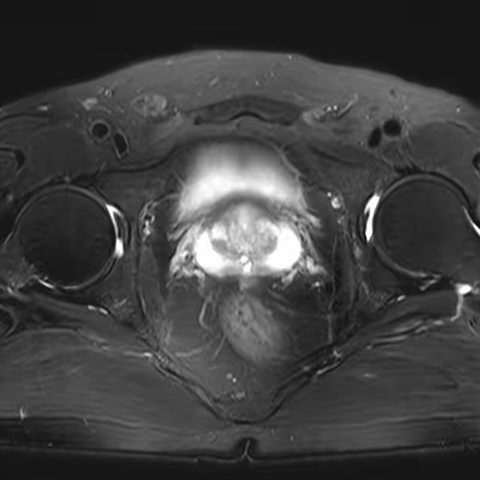

后入路结合VIP技术腹腔镜下根治性前列腺切除术